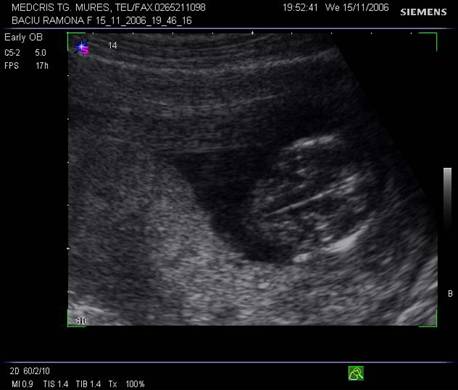

Fig. nr. 14. Sarcina 7 sapt( sageata indica embrionul )